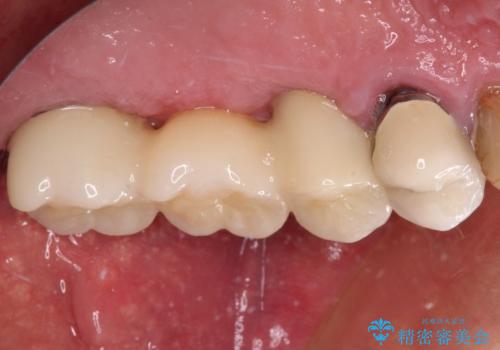

抜歯が必要な左右の奥歯 ブリッジとインプラントによる奥歯の補綴治療

左側は大臼歯2本と小臼歯1本が欠損しているため、インプラント2本を治療したブリッジ、右側は中間欠損であり、前後の歯も加療が必要であったためブリッジによる補綴治療を行うこととしました。

抜歯となった歯は全て神経が抜かれた歯であり、強大な咬合力によって破折したことが原因で抜歯となりました。

左右同時に強大な力を受けながらの治療であったため、仮歯の脱落や破損などがひんぱつしました。

治療後の現在は、より長い期間安定した状態を維持していただくため、就寝時マウスピースを装着するようお願いしております。